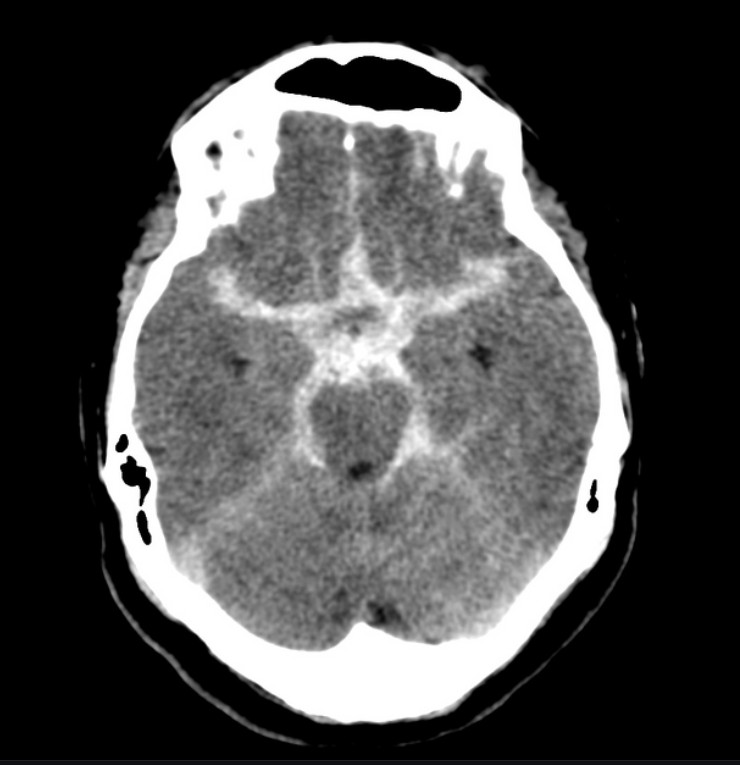

SAH의 brain CT 이미지

뇌지주막하출혈 – 출처 https://radiopaedia.org/